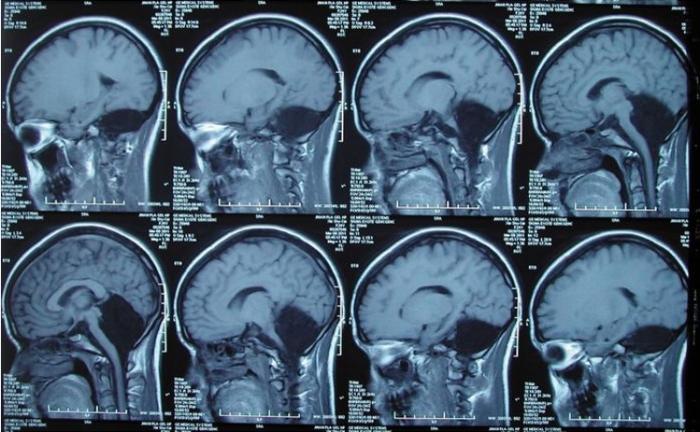

Doctorii din China au rămas perplecși în fața unui caz nemaipomenit. O tânără a trăit mai mult de 20 de ani fără creier!